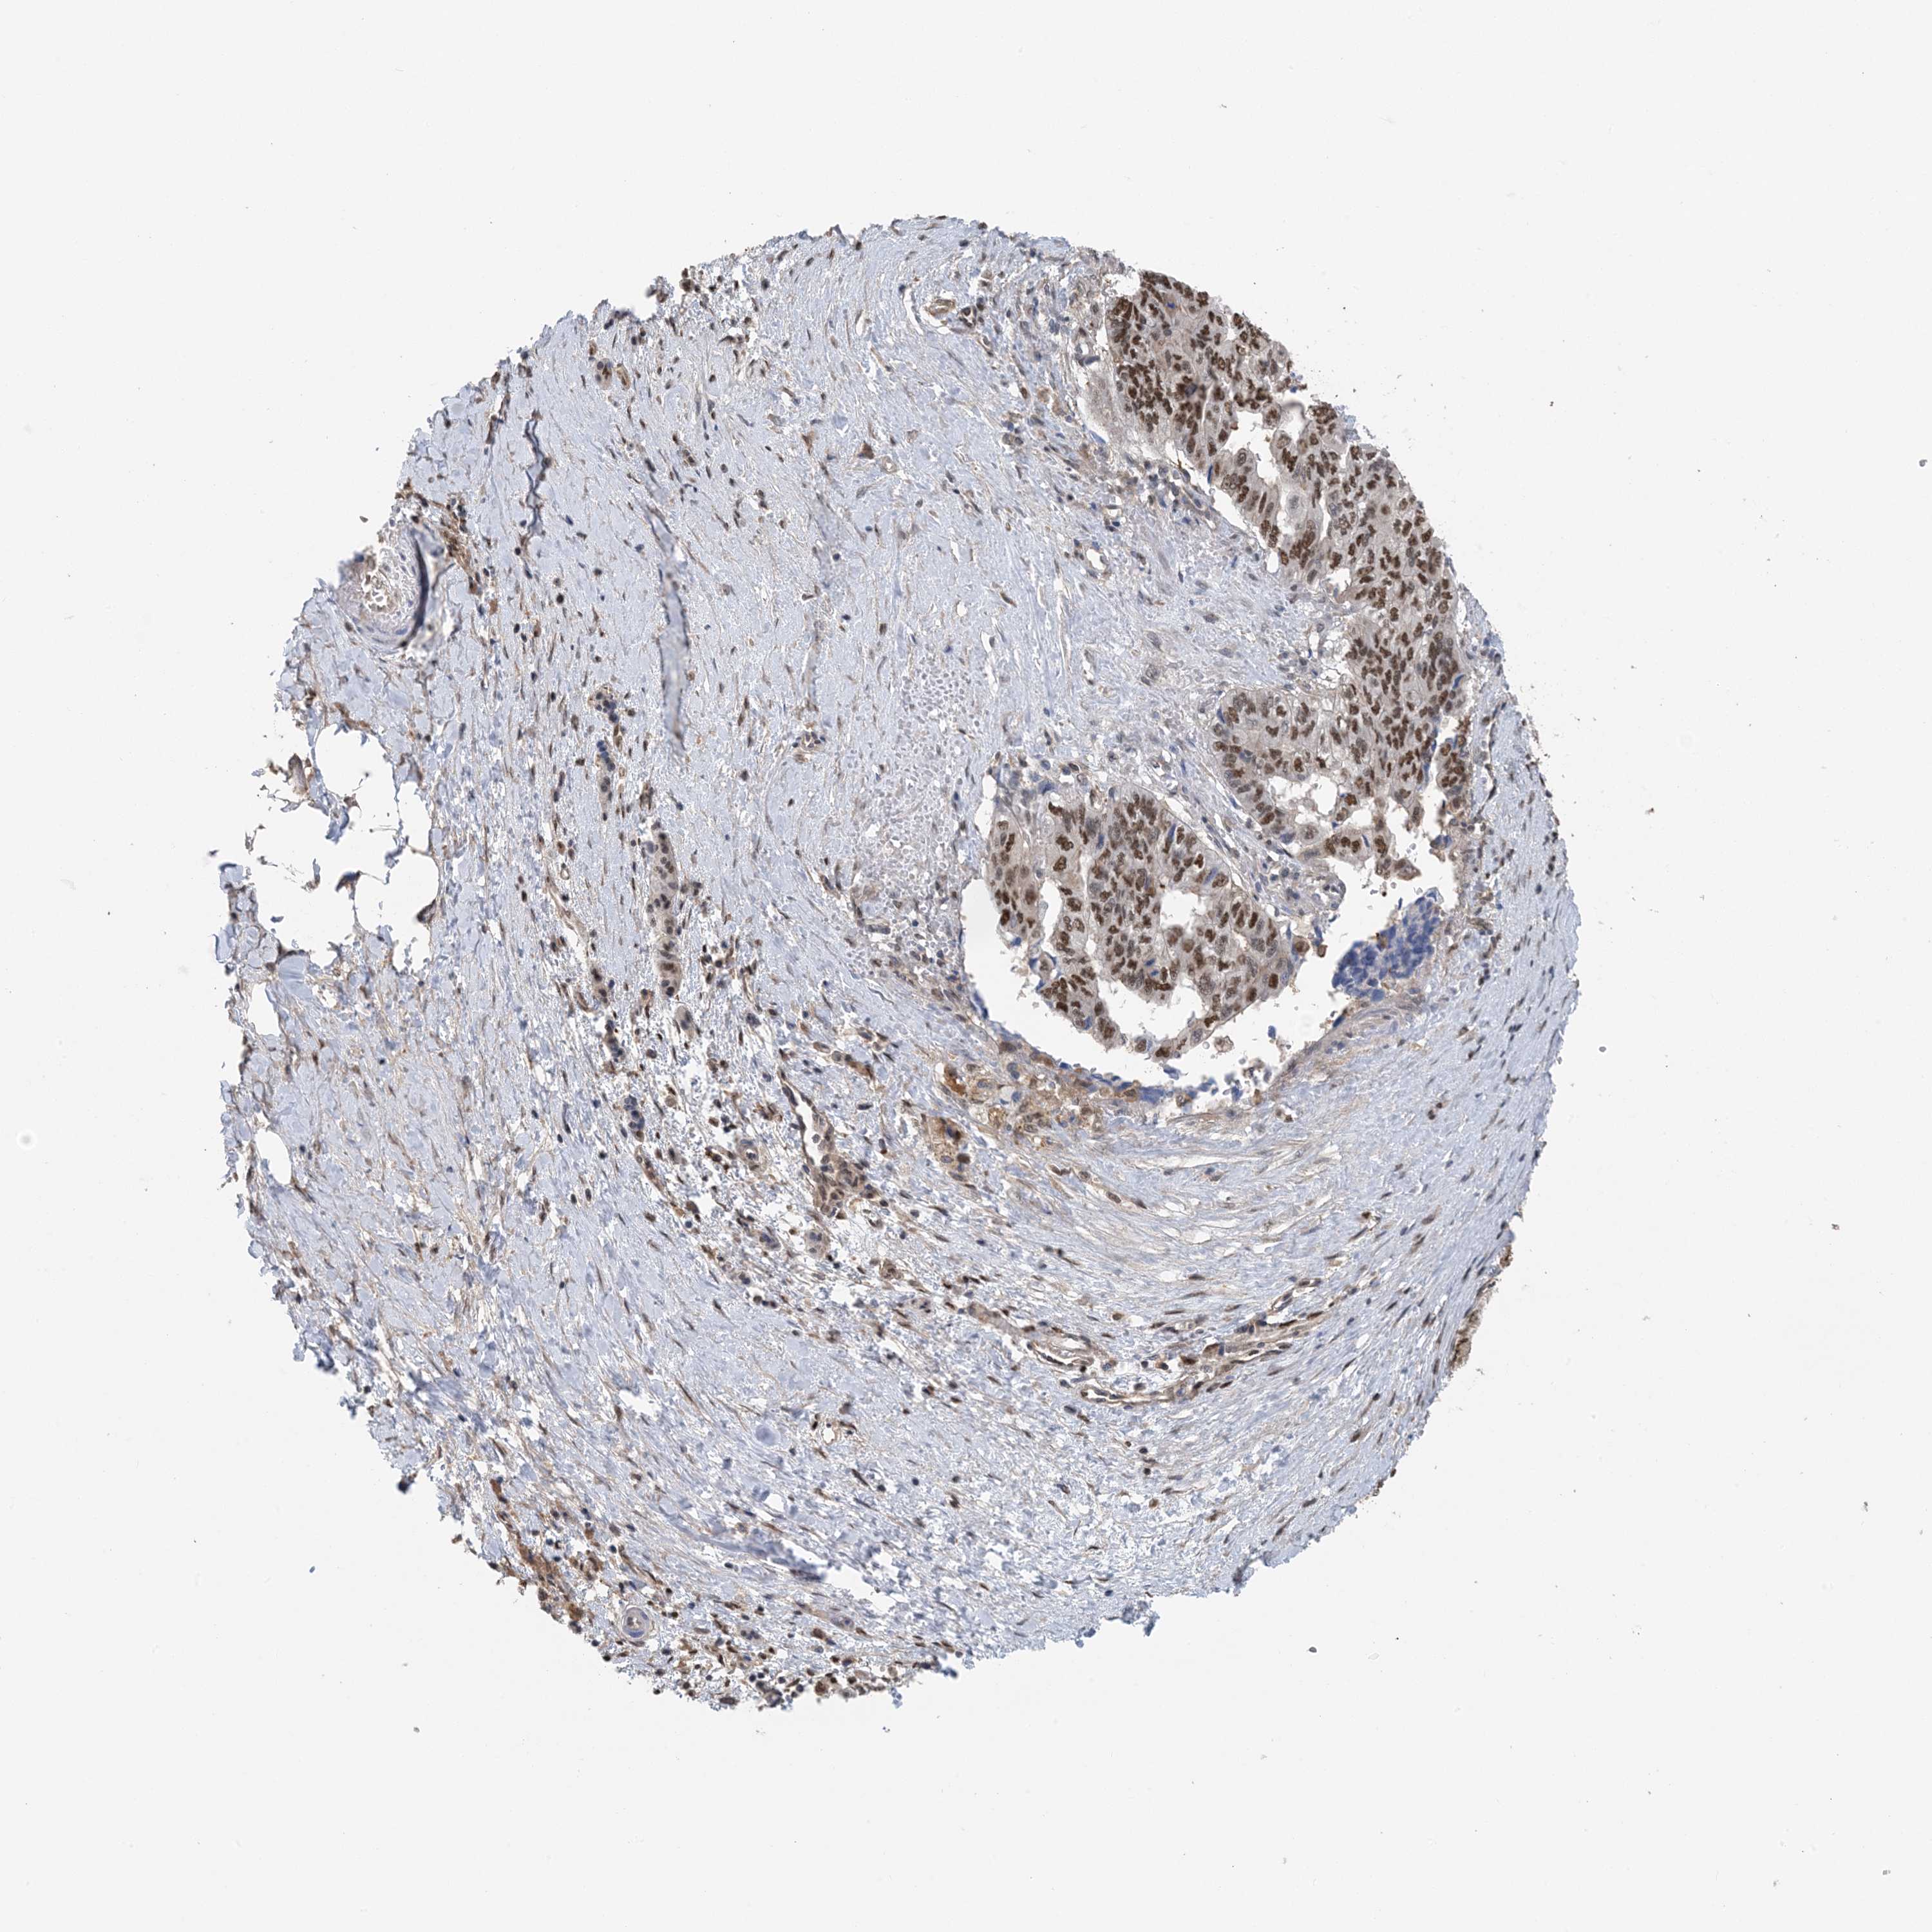

PANCREATIC CANCER - Protein expressioni

A mouse-over function shows sample information and annotation data. Click on an image to view it in a full screen mode. Samples can be filtered based on level of antibody staining by selecting one or several of the following categories: high, medium, low and not detected. The assay and annotation is described here.

Note that samples used for immunohistochemistry by the Human Protein Atlas do not correspond to samples in the TCGA dataset.

Antibody stainingi

Antibody staining in the annotated cell types in the current human tissue is reported as not detected, low, medium, or high, based on conventional immunohistochemistry profiling in selected tissues. This score is based on the combination of the staining intensity and fraction of stained cells.

Each image is clickable and will lead to virtual microscopy that enables deeper exploration of all samples and also displays staining intensity scores, fraction scores and subcellular localization as well as patient and tissue information for each sample.

Antibody HPA035063

Antibody HPA035064

Staining

High

Medium

Low

Not detected

Intensity

Strong

Moderate

Weak

Negative

Quantity

>75%

75%-25%

<25%

None

Location

Nuclear

Cytoplasmic/membranous

Cytoplasmic/membranous,nuclear

Adenocarcinoma, NOS